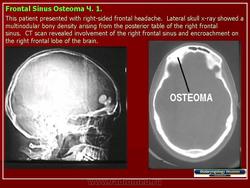

Компактные остеомы обычно располагаются в костях лицевого скелета. Остеомы могут быть обнаружены в любом возрасте, однако время обращения к врачу не соответствует началу заболевания. Вследствие медленного роста и отсутствия клинических проявлений остеомы нередко диагностируют только у взрослых, которые помнят, что заболевание возникло у них еще в детстве.

Рентгенодиагностика остеом, как правило, не представляет трудностей. Рисунок опухоли является продолжением рисунка самой кости. Деструктивные изменения и нарушение коркового слоя всегда отсутствуют.

Остеома лобной пазухи.